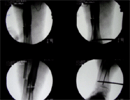

Intra

Op

Acute correction with fixator assisted nailing